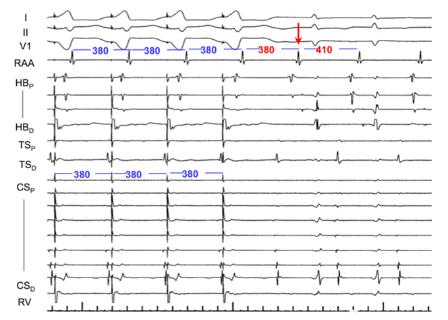

<p>关于图中VOP描述错误的是&#xff1f;</p>

关于图中VOP描述错误的是?

VOP的第一跳就终止了心动过速

可以大概率排除AT

室房被1:1带起

说明该心动过速的和心室高度相关

<p>关于图中电生理检查的过程描述正确的是&#xff1f;</p>

关于图中电生理检查的过程描述正确的是?

VOP反应为VAAV,诊断AT

室房未被1:1带起

RAA通道上第4跳A是由最后一跳起搏的V传的

VOP反应为VAVA,排除AT